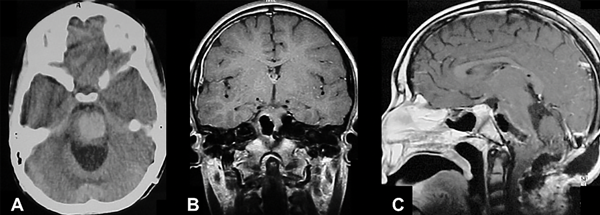

Figura 1. Tres casos de cavernomas cerebrales supratentoriales superficiales operados. A) y B) Imágenes prequirúrgicas y postquirúrgicas del paciente número 3: femenina de 7 años, que consulta por crisis parcial motora en miembro inferior derecho y crisis de ausencias. Secuencia SWI hipointensa correspondiente a restos hemáticos, secuencia T1 con contraste EV libre de lesión. C) y D) Imágenes pre y postquirúrgicas del paciente número 6: masculino de 2 años que es derivado por estatus convulsivo. TC de cerebro sin contraste que muestra extensa lesión parietotemporal derecha espontáneamente hiperdensa, con desvío de línea media y adelgazamiento de calota craneana homolateral. RM de cerebro con contraste EV, se observa cavidad porencefálica postoperatoria, recuperación de anatomía ventricular. E) y F) Imágenes pre y postquirúrgicas del paciente número 1: masculino de 12 años que consulta por crisis parciales simples motoras, que posteriormente generalizan. RM de cerebro con contraste EV que muestra lesión hiperintensa en región frontoopercular derecha. RM de cerebro con contraste EV postoperatoria, exéresis completa.

Las MC se localizan en el compartimento supratentorial entre el 60-90 %,1,3,9,17,24 y en nuestra serie fue del 61% (ver Figura 1). Acciarri y cols. encontraron predominio por el lado izquierdo en casos sintomáticos, mientras que nosotros no tuvimos predisposición por ningún lado.3 De nuestra serie, el 8% tuvo diagnóstico incidental, un porcentaje bajo e incluso menor a lo reportado por Bigi y cols. con un 14.2%.9